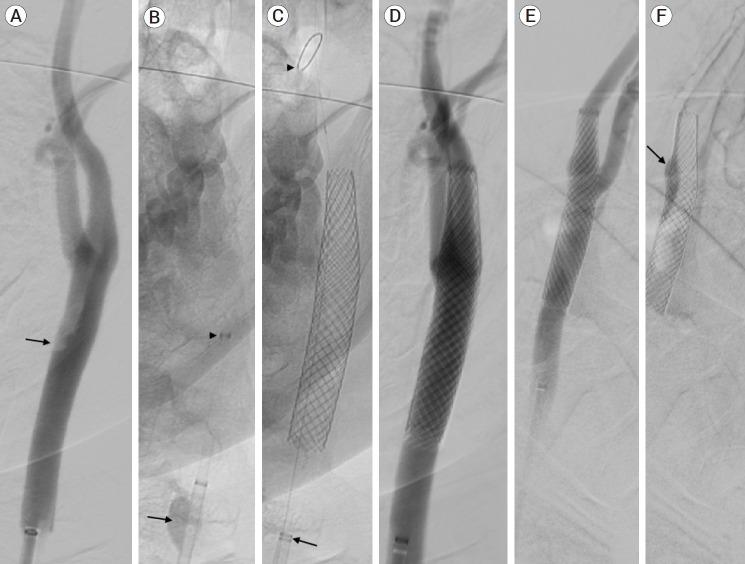

The carotid web (CW), an intimal variant of fibromuscular dysplasia (FMD), is recognized as a cause of stroke and with a high-risk of stroke recurrence. Other names are carotid-bulb atypical FMD, carotid (bulb) diaphragms and it is described like a shelf of tissue from the posterior wall of the carotid bulb. Here we present a case of a young patient with recurrent stroke, with no other risk factors that was diagnosed with a common CW.

颈动脉纤维肌性发育不良内膜变异型(CW)被认为是中风的一个病因,且中风复发风险高。其他名称有颈动脉球部非典型纤维肌性发育不良、颈动脉(球部)隔膜,它被描述为从颈动脉球后壁突出的一层组织。在此,我们报告一例年轻的复发性中风患者,该患者无其他风险因素,被诊断为常见的CW。